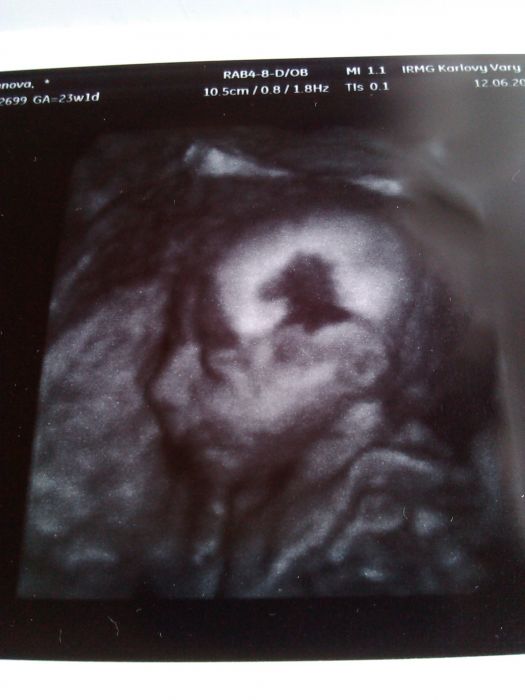

Ahojte tak 3D ultrazvuk pěknej nechtěl se nám teda sice otočit čelem ale aspoň z boku, byl to hezký zážitek